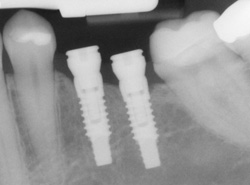

An implant is a synthetic tooth root in the shape of a post that is surgically placed into the jawbone. The “root” is usually made of titanium (the same material used in many replacement hips and knees), a metal that is well suited to pairing with human bone. A replacement tooth is then fixed to the post. The tooth can be either permanently attached or removable. Permanent teeth are more stable and feel more like natural teeth.

Implants are versatile. If you are only missing one tooth, one implant plus one replacement tooth will do the trick. If you are missing several teeth in a row, a few strategically placed implants can support a permanent bridge (a set of replacement teeth). Similarly, if you have lost all of your teeth, a full bridge or full denture can be permanently fixed in your mouth with a strategic number of implants.